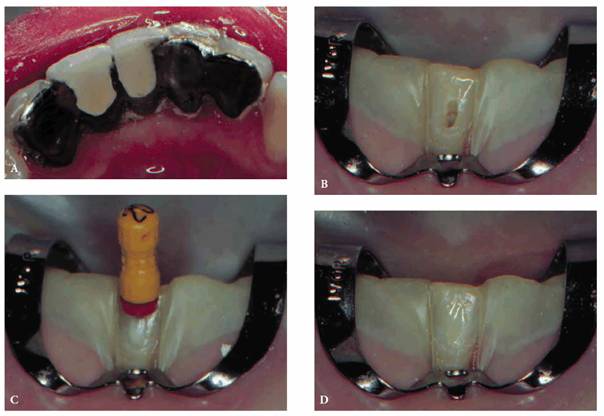

weakening the bond is great. In most cases, a new #2 or #1558 carbide bur and a

copious water spray will minimize heat and reduce the vibration, which is the

cause of debonding. Occasionally, it is more practical to prepare the access

cavity through the labial surface, in particular when dealing with lower

incisor teeth that are lingually inclined (Figures 19-50A

to D). The

distinct advantage of direct access without disturbing the casting is

immeasurable. The opening can then be repaired with a light-cured composite

resin. Cosmetically, the lip and smile lines should be considered before using

this approach. Communicating the benefits of this approach and having the

patient accept the technique before proceeding are essential.

Figure 19-50A to D: Access alternative for an etched cast bridge: (A) five-unit bridge, (B) access cavity prepared on labial surface, (C) measurement file in place, and (D) composite resin repair of access cavity.